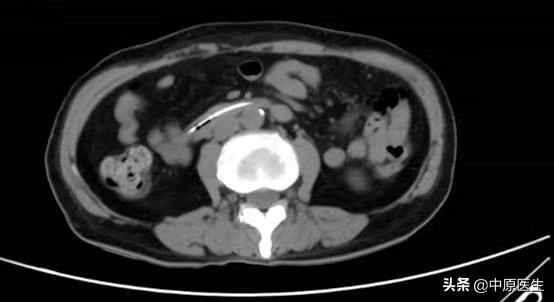

经过思考,我们认为可能与下列因素有关:1、因为是突然出现,是不是空肠营养管脱出?或者是空肠远端梗阻?立即完善胃镜及腹部CT检查,结果未发现空肠营养管脱出,也未发现明显的梗阻;2、难道是导管发生了破损,导致营养液漏到胃内?向空肠营养管内输注少量亚甲蓝,减压管内也引流出了蓝色液体,进一步完善小肠造影,结果回示:营养管瘘,同时也未发现肠道远端梗阻;根据这样的检查结果,我们考虑胃空肠营养减压一体管破损,于是立即行经胃镜给予更换管路。